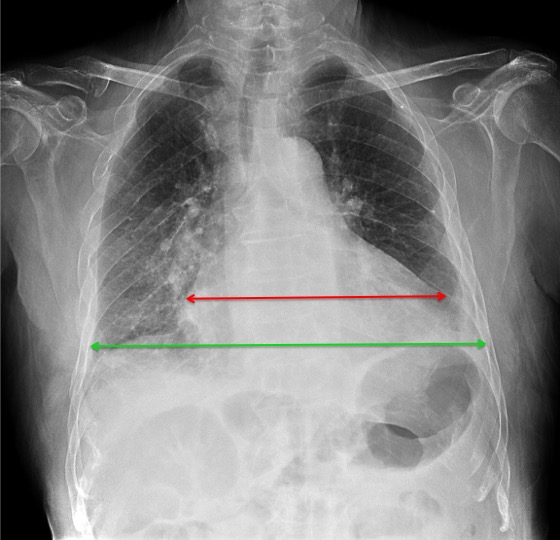

CASO: sospecha de neumonía.

Hallazgos:

- En un principio podríamos decir que existe un aumento de densidad retrocardiaco que podría ser compatible con condensación neumónica a dicho nivel, sin embargo estamos ante una placa poco inspirada, lo cual puede llevarnos a cometer errores diagnósticos.

- Se recomendó volver a realizar la radiografía, observar a continuación:

Ya no se observa el aumento de densidad retrocardiaco, la placa es normal.

INSPIRACIÓN: Una placa bien inspirada es aquella en la que se observar 6-7 arcos costales anteriores o 10-11 arcos costales posteriores. Lo contrario puede producir imágenes falsas de condensaciones o de seudocardiomegalia.